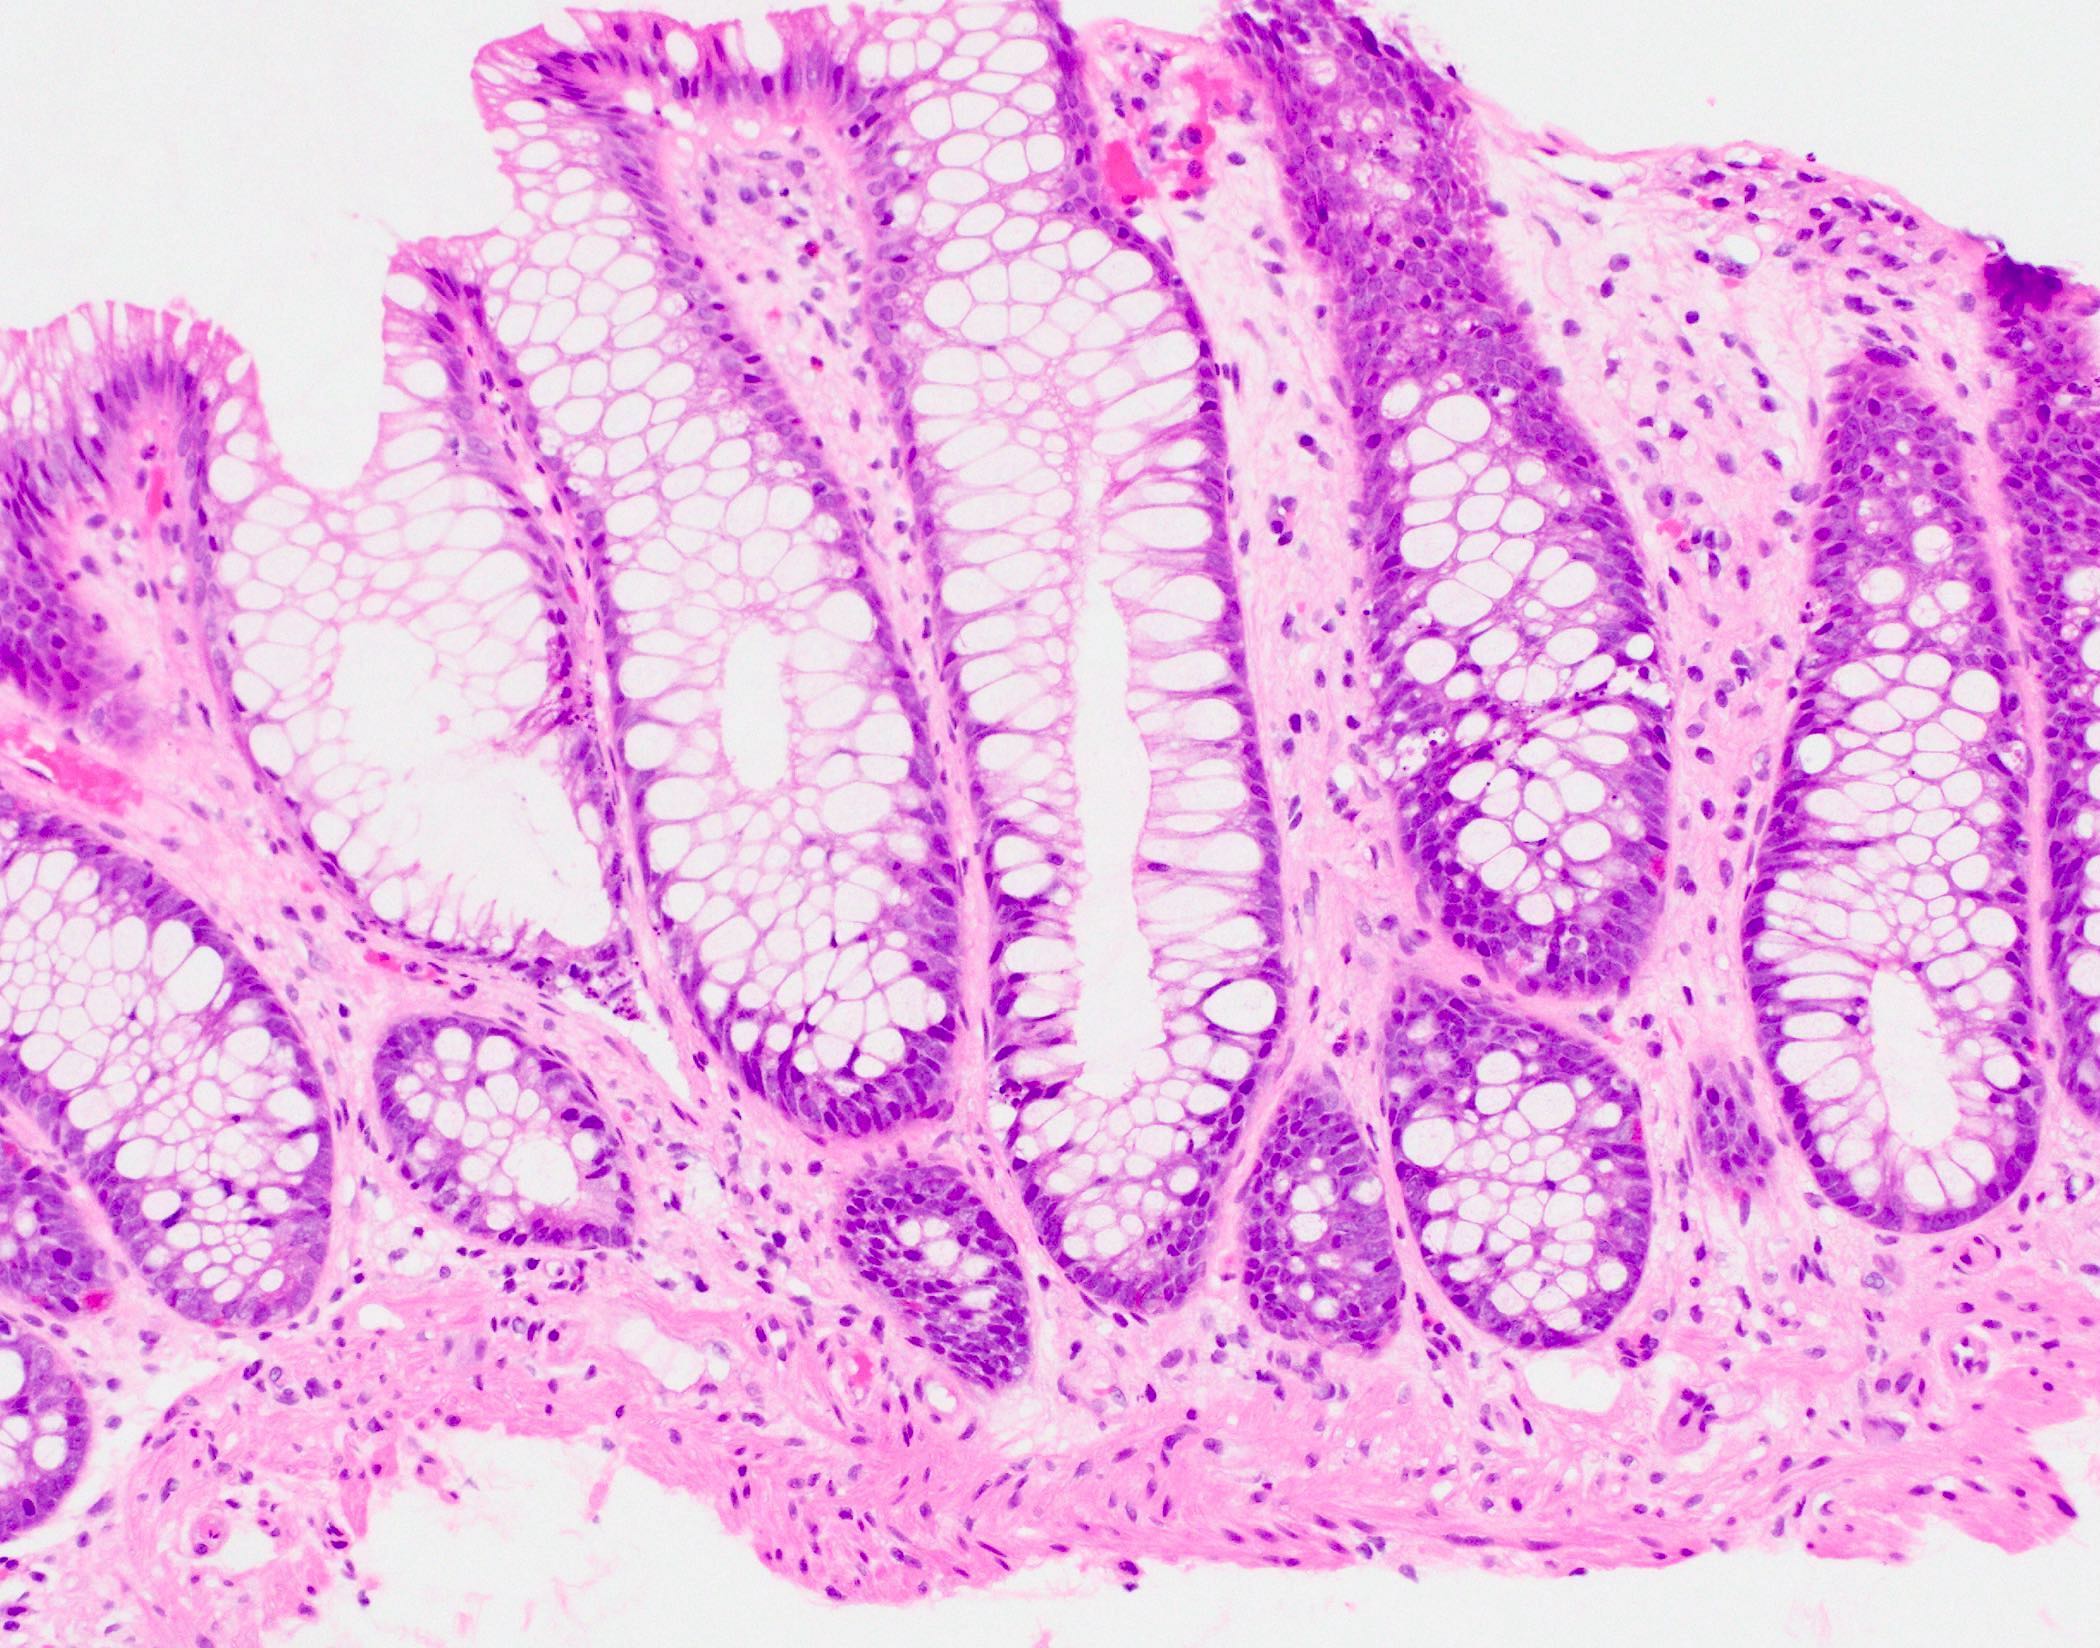

- Characteristic histologic features include crypt apoptosis, crypt dropout and ulceration (Biol Blood Marrow Transplant 2015;21:589)

- Inflammation is generally sparse

- Apoptosis in the colon is not specific to graft versus host disease and the lower diagnostic threshold is debated

- National Institute of Health proposes ≥ 1 apoptotic body per biopsy fragment (Biol Blood Marrow Transplant 2015;21:589)

- Others propose > 6 apoptotic bodies per 10 contiguous crypts for definitive diagnosis of graft versus host disease (Am J Surg Pathol 2013;37:539)

- Cases with ≤ 6 apoptotic bodies per 10 contiguous crypts are considered indeterminate for graft versus host disease (Histopathology 2016;69:802)

- Grade I: crypt apoptosis without crypt dropout

Microscopic (histologic) images